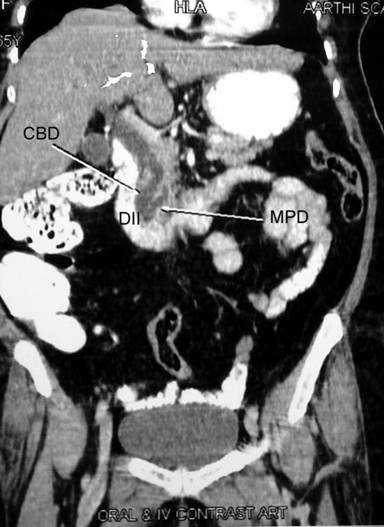

A 45-year-old male presented to the out-patient department with jaundice of 30-day duration. He had no abdominal pain, but gave a history of high colored urine along with pale stools. He also had pruritus along with significant weight loss of 15 kg over the previous two months. His past surgical history was significant for a history of laparoscopic cholecystectomy one year ago; the procedure and the post-operative period was uneventful. On examination, his vital parameters were stable, and apart from icterus, his general examination was unremarkable. Abdomen examination was unremarkable apart from healthy port-site scars. Per-rectal examination revealed pasty pale stools. His complete hemogram and renal function tests were within normal limits. His liver function tests revealed an increased direct fraction of bilirubin (6.08 mg/dL; reference range: 0-1 mg/dL), along with a raised alkaline phosphatase (722 IU/L; reference range: 80-290 IU/L) and gamma glutamyltranspeptidase (243 IU/L; reference range: 7-32 IU/L). An esophagogastroduodenoscopy was done which revealed a prominent ampulla. A side-viewing-scopy of the duodenum was done, which showed an ulcerated growth at the ampulla, a biopsy of which was inconclusive, with atypical cells. Imaging of the abdomen showed intrahepatic and extrahepatic biliary radical dilatation with obstruction at the level of the ampulla. The main pancreatic duct was also dilated up to the ampulla (Figure 1). CA 19-9 was done which was elevated at 74.28 ng/mL (reference range: 0-10 ng/mL). The patient was optimized and was taken up for a planned pancreaticoduodenectomy for the ampullary growth. Intraoperatively, on evaluation of the superior border of the pancreas, common hepatic artery was found to be absent. Further kocherization and careful dissection of the hepatoduodenal ligament revealed a replaced common hepatic artery arising from the superior mesenteric artery which was coursing through the uncinate process, posterior to the duodenum and portal vein. The artery crossed the portal vein laterally to lie anterior to the common bile duct at the superior border of the pancreas, where it divided into the left and right hepatic arteries (Figure 2). The gastroduodenal artery was absent; the right gastric artery arose from the left hepatic artery. Following an extended kocherization and hilar dissection, complete course of the artery was delineated. Pancreas was transected at the neck anterior to the portal vein and the uncinate process was successfully dissected free from the common hepatic artery (Figure 3). A pylorus preserving pancreaticoduodenectomy was completed. Patient developed grade I delayed gastric emptying (International Study Group for Pancreatic Surgery Criteria), which improved with conservative management. Rest of his post operative period was uneventful, and he was discharged on the 14th postoperative period. Histopathology revealed an ampullary adenocarcinoma, with all margins being free from tumor.

Figure 1. Contrast enhanced CT abdomen showing dilatation of common bile duct (CBD) and main pancreatic duct (MPD), suggestive of obstruction at the level of the ampulla. DII: second part of duodenum |